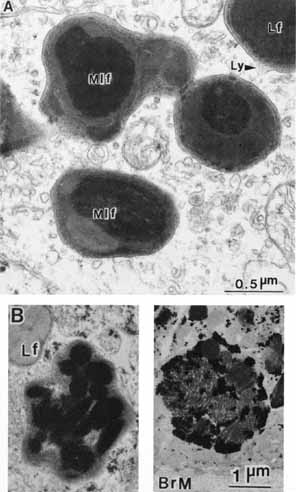

pigmentation. Pigment Cell Res 12:219–236, 1999 65. Schraermeyer U, Peters S, Thumann G, Mociok N, Heiman K: Melanin granules of the retinal pigment epithelium are connected with the

lysosomal degradation pathway. Exp Eye Res 68:237–245, 1999 66. Eldred GE: Lipofuchsin and other lysosomal storage deposits in the retinal pigment

epithelium. In Marmor MF, Wolfensberger TJ, (eds): The Retinal Pigment Epithelium. New York: Oxford University Press, 1998:651–668 67. Feeney-Burns L, Hilderbrand ES, Eldridge S: Aging human RPE: Morphometric analysis of macular, equatorial, and peripheral